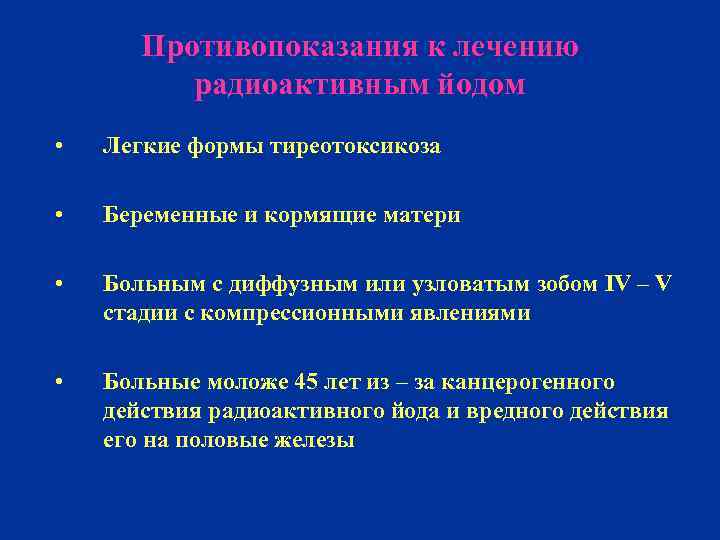

Противопоказания к лечению радиоактивным йодом • Легкие формы тиреотоксикоза • Беременные и кормящие матери • Больным с диффузным или узловатым зобом IV – V стадии с компрессионными явлениями • Больные моложе 45 лет из – за канцерогенного действия радиоактивного йода и вредного действия его на половые железы

Противопоказания к лечению радиоактивным йодом • Легкие формы тиреотоксикоза • Беременные и кормящие матери • Больным с диффузным или узловатым зобом IV – V стадии с компрессионными явлениями • Больные моложе 45 лет из – за канцерогенного действия радиоактивного йода и вредного действия его на половые железы